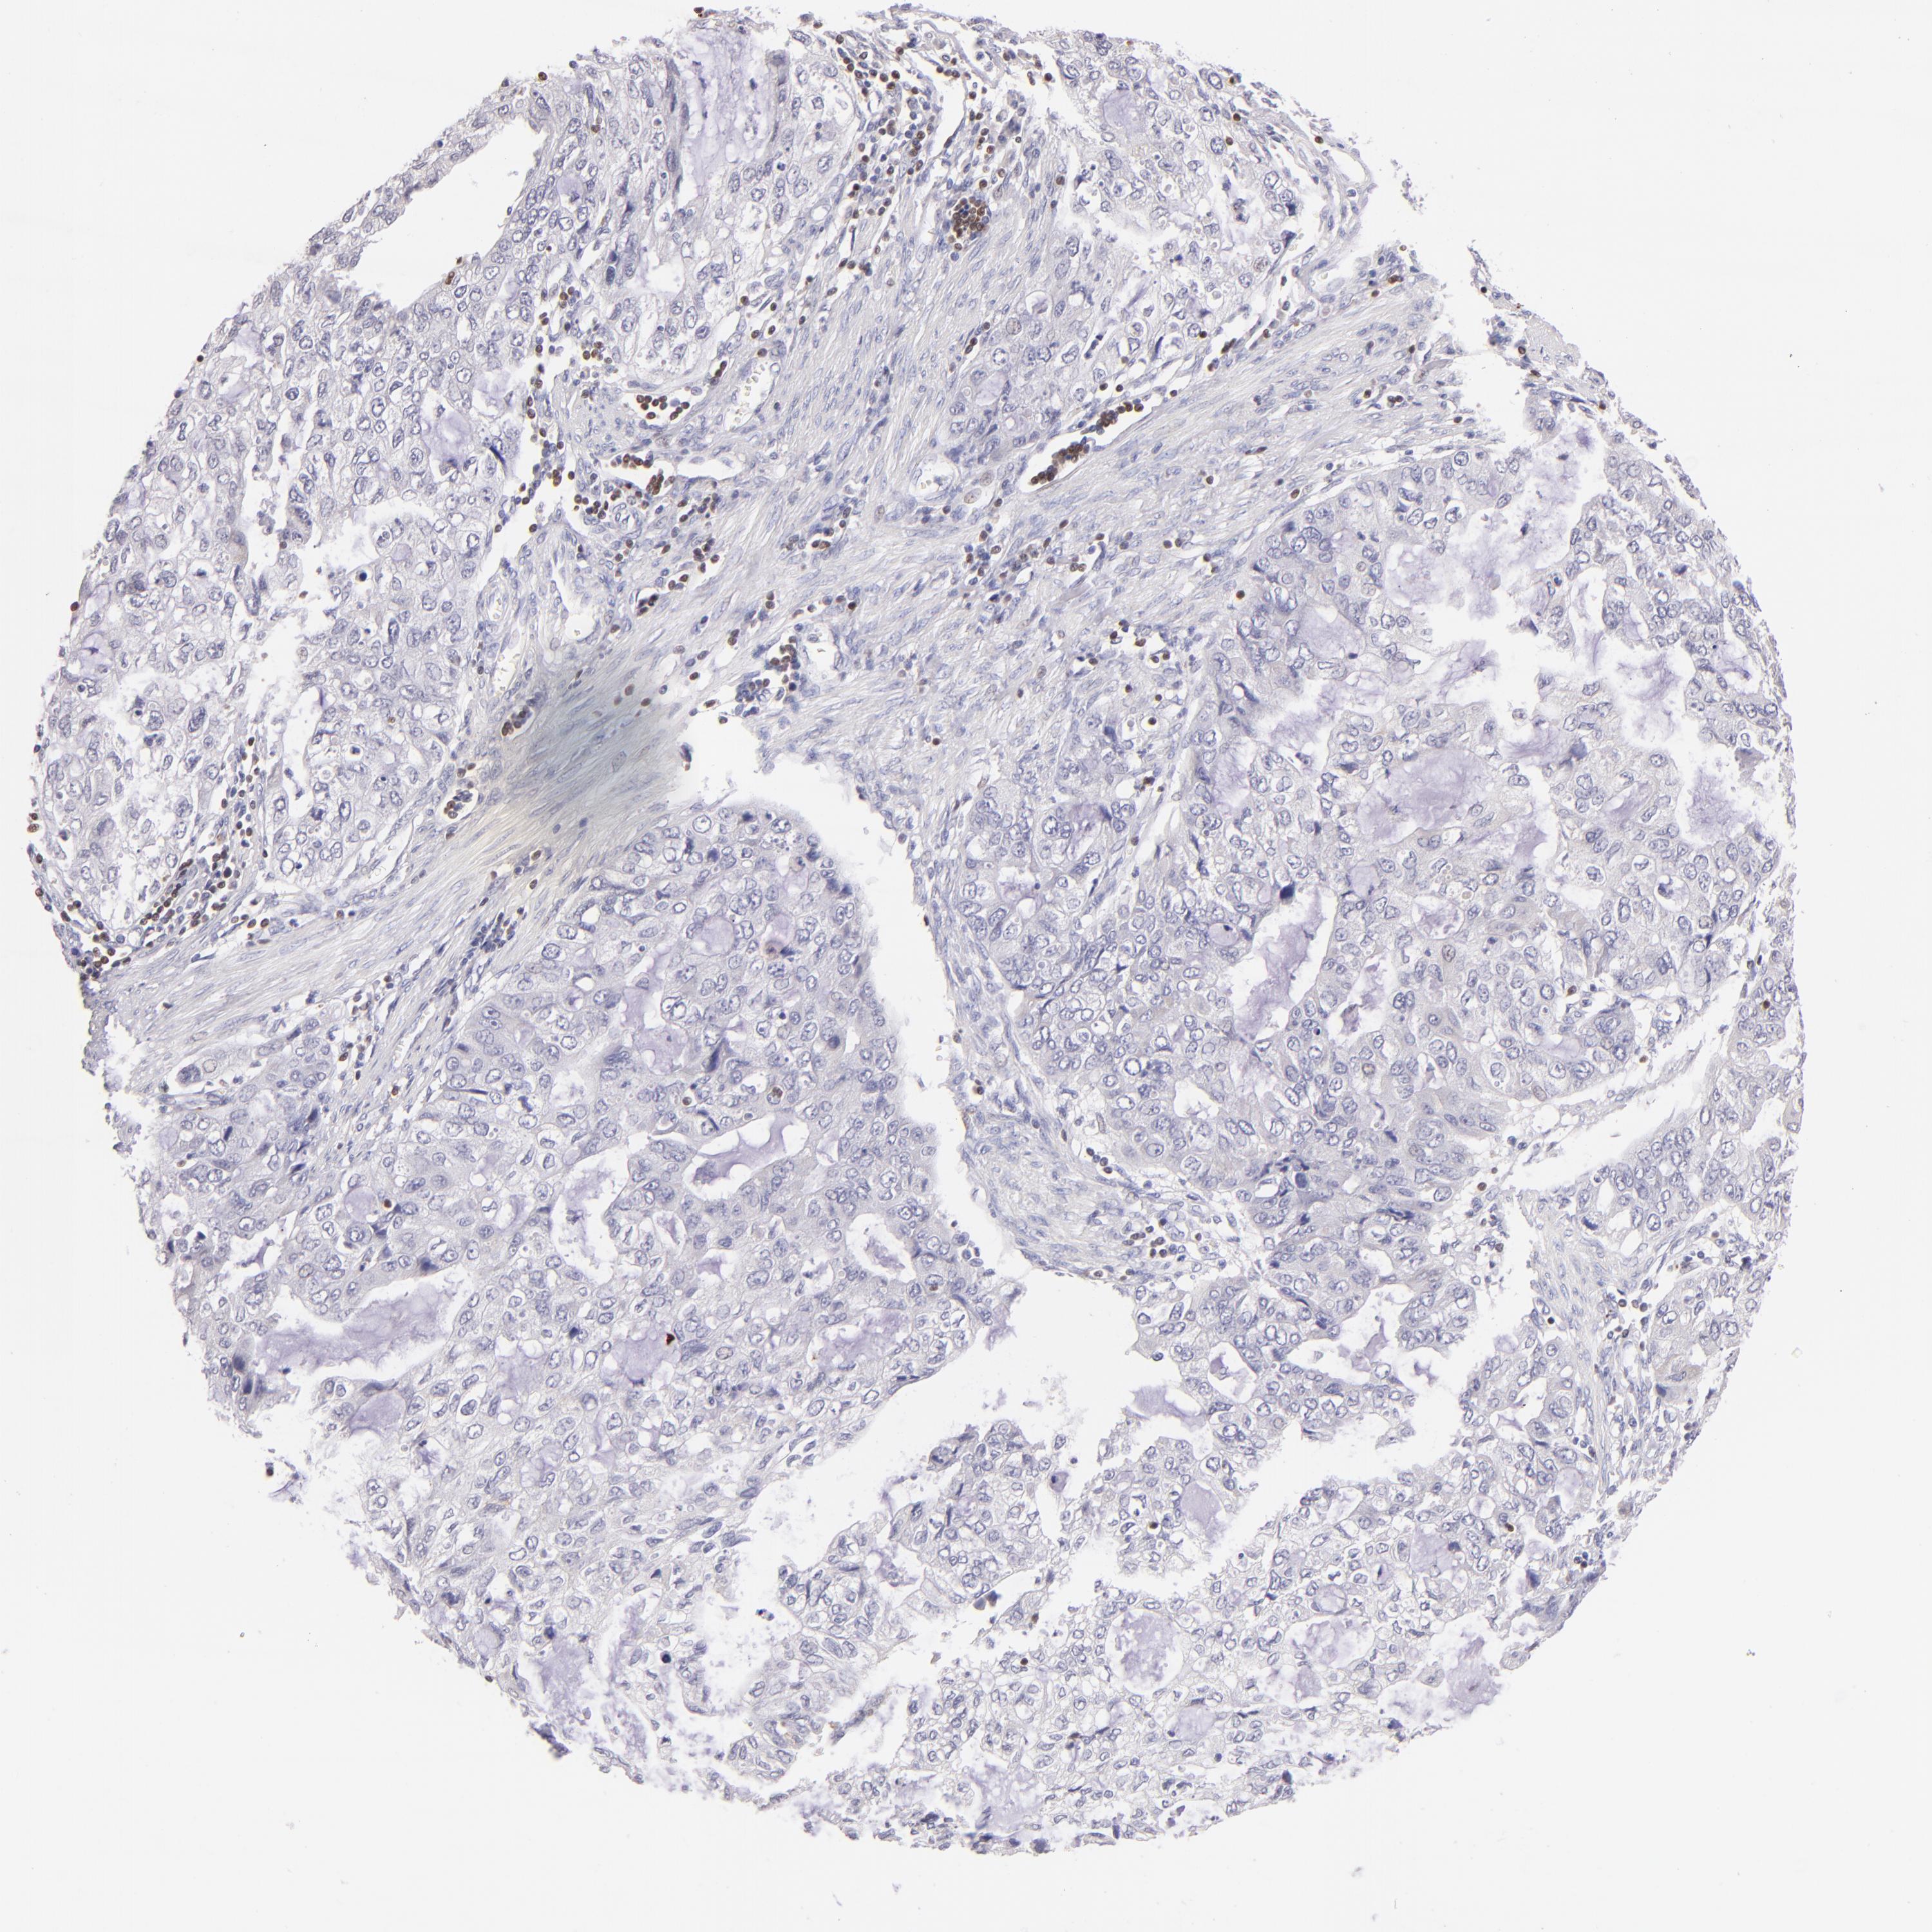

STOMACH CANCER - Protein expressioni

A mouse-over function shows sample information and annotation data. Click on an image to view it in a full screen mode. Samples can be filtered based on level of antibody staining by selecting one or several of the following categories: high, medium, low and not detected. The assay and annotation is described here.

Antibody stainingi

Antibody staining in the annotated cell types in the current human tissue is reported as not detected, low, medium, or high, based on conventional immunohistochemistry profiling in selected tissues. This score is based on the combination of the staining intensity and fraction of stained cells.

Each image is clickable and will lead to virtual microscopy that enables deeper exploration of all samples and also displays staining intensity scores, fraction scores and subcellular localization as well as patient and tissue information for each sample.

Antibody HPA003134

Antibody CAB002625

Staining

High

Medium

Low

Not detected

Intensity

Strong

Moderate

Weak

Negative

Quantity

>75%

75%-25%

<25%

None

Location

Nuclear

Cytoplasmic/membranous

Cytoplasmic/membranous,nuclear

Adenocarcinoma, NOS